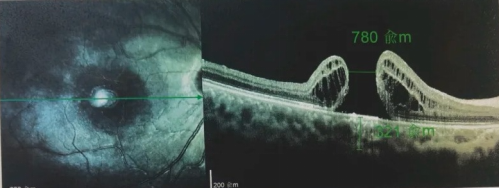

由于自身患有頸椎病,每次術(shù)后長期的趴睡都讓他痛苦不堪。為了尋求更好的治療,吳爺爺來到廈門大學(xué)附屬廈門眼科中心,找到了眼外傷及眼底病2科的李海波博士后。此時(shí),吳爺爺右眼的黃斑裂孔已經(jīng)持續(xù)擴(kuò)大到780μm,演變?yōu)殡y治性的大裂孔。

最讓吳爺爺難以置信的是:術(shù)后只需保持平躺24小時(shí)!第二天復(fù)查時(shí),眼底鏡及OCT檢查清晰顯示——那個(gè)折磨了他大半年的大裂孔,竟然閉合了!且吳爺爺?shù)挠已垡暳τ辛嗣黠@的改善,術(shù)后3天已經(jīng)可以看到 0.15。